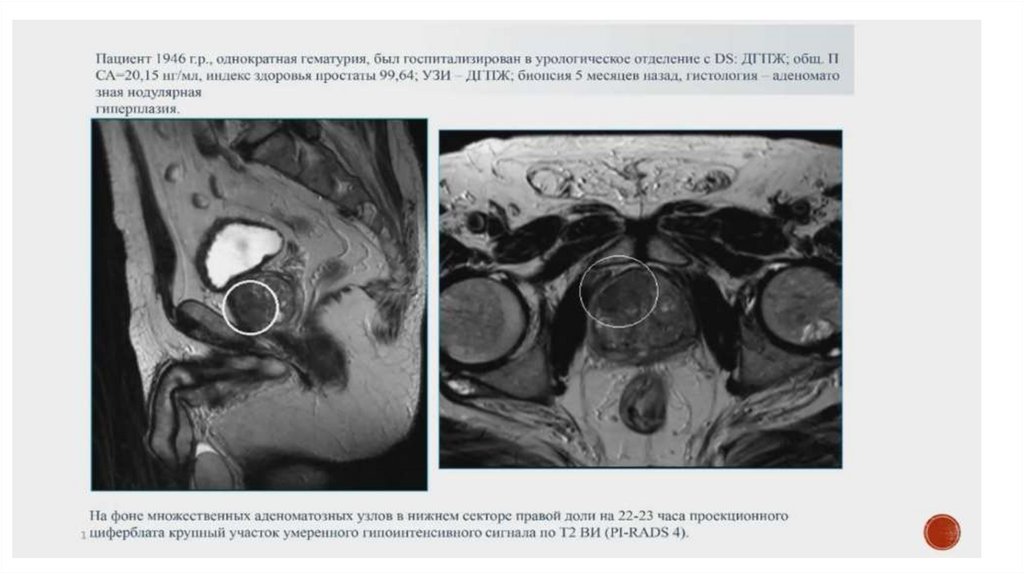

После узи мрт можно делать только после 11.5 мес. (поэтому лучше до сделать)